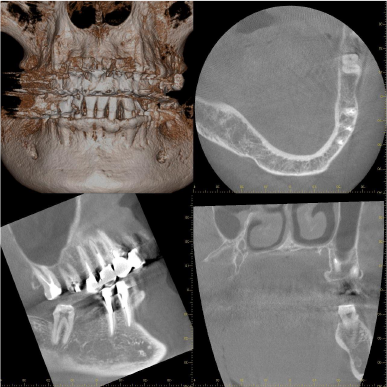

右の下奥歯には深い歯周ポケットが残っています。

レントゲン写真では矢印の位置ぐらいには骨がありそうに見えますが、CTにて詳しく調べてみると矢印の位置まで歯周病が進行して骨が破壊されていることがわかります。

患者さんと相談した結果、歯周組織再生療法を希望されたため、施術させていただくことになりました。

術前で破壊されていた部分に骨の再生が認められるため、黒かった部分が白くなっていることがわかります。

再生療法時 骨が失われている部位 骨が失われている部位 |

再生療法後 再生した部位 再生した部位 |

| 失われていた骨の再生が認められます。 | |

CT所見で見られたのと同様に再生療法を行った部位にみられた骨欠損は骨様組織にて満たされていることがわかります。